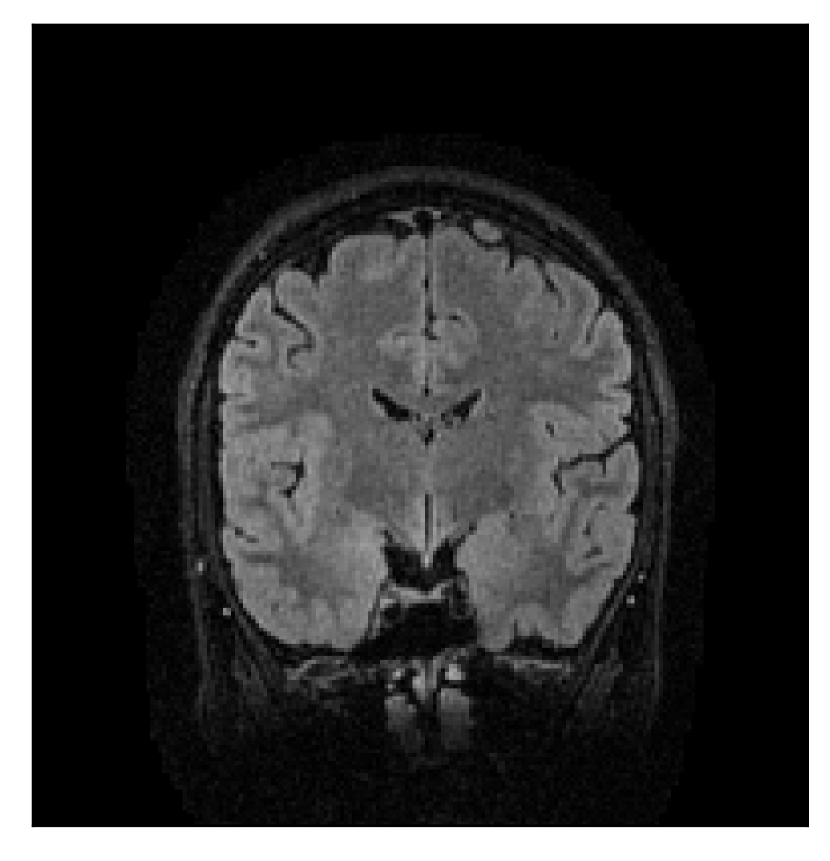

4.1 Experiment 1: robustness test

We gather the results for the robustness test described in Section 3.1 (volunteer 1) in Figures 2, 4, and 6 for motion corruption mechanisms associated to one, two, and five changes of position, respectively. Furthermore, we juxtapose the corrected images with varying degrees of corruption in Figure 8. We observe that the proposed method consistently ameliorates the corrupted scan. The quality indexes based on PSNR and SSIM show only a modest decrease in correction quality as a function of motion complexity (Figure 8).

| Section 3.1, Figure 2 | Sagittal | 23.94 | 27.95 | 0.7068 | 0.7936 |

| Coronal | 26.66 | 29.82 | 0.7653 | 0.8332 | |

| Axial | 25.40 | 30.16 | 0.7616 | 0.8490 | |

| Section 3.1, Figure 2 | T2-FLAIR | Completely corrected | Some blurring | No additional artifacts | Good grey white matter differentiation |